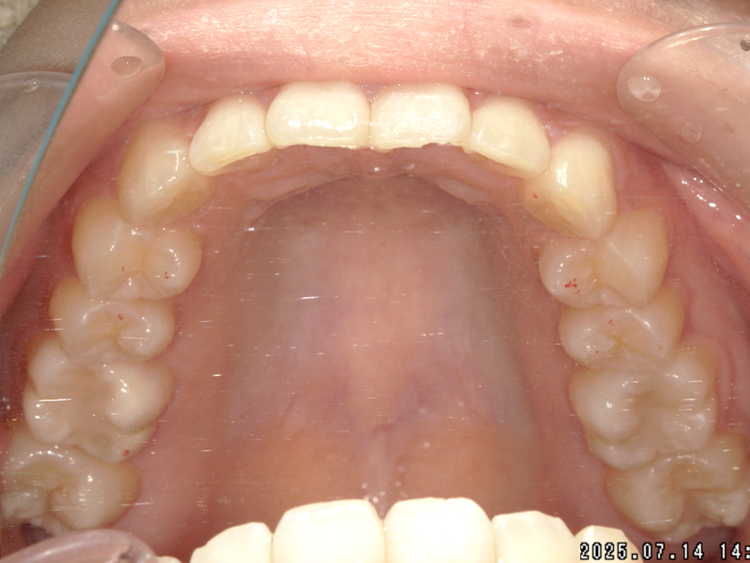

症例4

Before

After

| 主訴 | 上下前歯のがたつき |

| 年齢 | --- |

| 治療 期間 |

約9ヶ月 |

| 治療 内容 |

インビザラインiGoで上下顎の治療。 |

| 治療費 | ¥550,000(税込)/調整料含む |

| 治療のリスク | 矯正終了後は、リテーナーを指示通りに使用し、歯の後戻りを防ぐ必要があります。 |